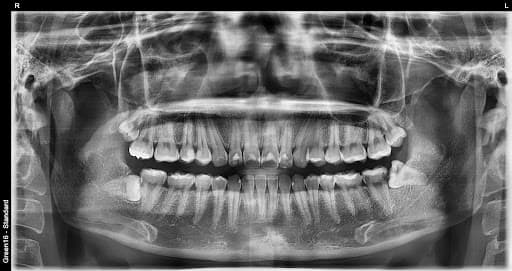

复杂的阻生智齿 - 即使深埋在牙龈中也没问题

贴近神经的智齿 - 无需担心神经损伤,安全拔除

水平阻生智齿 - 即使是横向生长的困难案例也可以处理

凭丰富的拔牙经验,

安全解决疑难案例

是的,可以。延世温雅牙科拥有丰富的拔牙经验和大学医院级别的系统来处理疑难病例。其他诊所转介到大医院的横向阻生和完全埋伏等困难病例,我们都能使用精确的3D CT诊断安全拔除。